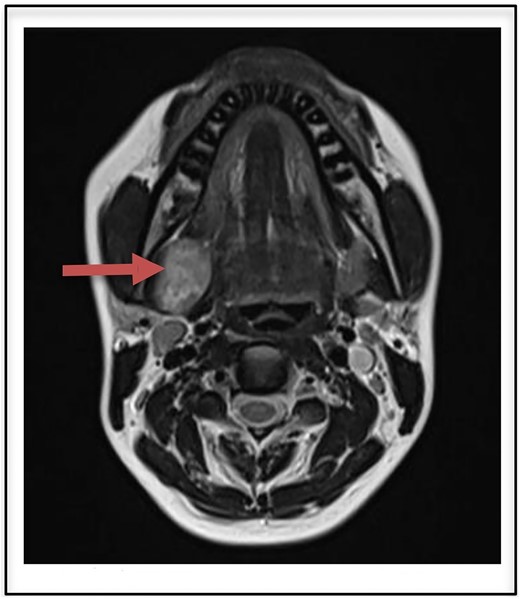

Routine laboratory investigations were normal. Ultrasound scan of the neck region showed a hypoechoic lesion 2.9 × 2.7 cm in the right submandibular gland taking internal vascularity without calcification or necrosis. MRI imaging revealed a T2 heterogeneously hyperintense lesion with internal areas of low signal areas giving rise to a fascicular pattern that is typical of nerve sheath tumors (Fig. 1). On correlation with ultrasound, the lesion appears heterogeneously hypogenic with moderate internal vascularity.

T2 heterogenously hyperintense oval shaped well circumscribed lesion measuring 2.9 × 2.7 cm on MRI (arrow).